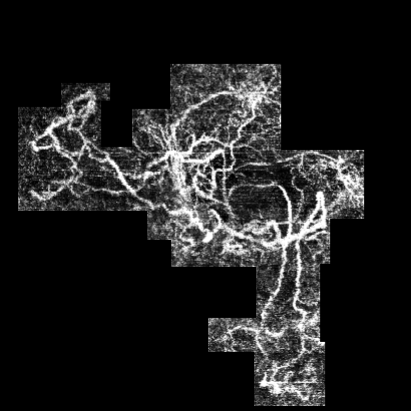

We illustrate here how the processing steps lead to the binary image, which contains essential information about the blood vessels. Fig. 9 shows the steps involved in the Data Cleaning phase and Otsu Thresholding.

Fig. 10 presents the image processing techniques and their outcomes at each iteration. The grayscale images progressively approach a binary representation, as seen after the application of multiple binarization techniques. The salt and pepper filter removes part of the noise. In the final image, all components are colored in a way that highlights the principal component. Any remaining noise is removed in Fig. 11, which also shows the result after applying region filling techniques.

To assess the performance, we used the Jaccard Distance = and the Dice coefficient to compare the two sets of data in our scenario: the 1st batch and the 3rd one. A Jaccard Index is 0.8912, suggesting that 89.12% of the pixels identified during the Data Cleaning and Image processing module were also identified by the ophthalmologist. The Dice Coefficient ranges from 0 to 1, where 0 indicates no overlap, and 1 indicates complete overlap (identical sets). The value of the Dice coef = 0.92 is very high, which suggests that the two sets A and B have a large overlap.

The pictures represent the right eye of a patent suffering from nAMD. The first image - (a) from Fig. 12 - was taken on June 27th 2023 and the second one - (c) from Fig. 12 - was taken almost a year later, on June 11th 2024.